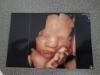

В 33, также на днях ходила в 36 удалось шикарные снимки получить 😍